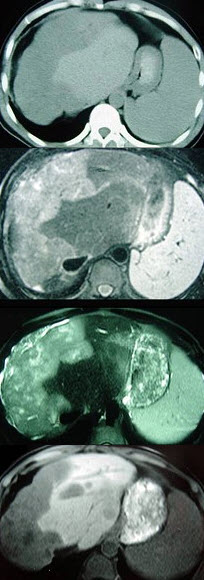

女性,72岁,腹胀不适1年,加重伴恶心、呕吐、乏力1个月,影像检查如图,最可能的诊断为( )

A:肝硬化腹水

B:原发性肝癌

C:肝血管瘤

D:巴-希综合征

E:局灶脂肪肝